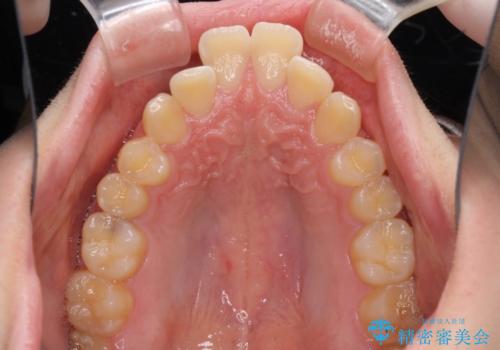

出っ歯と八重歯 目立たない裏側装置でスッキリとした口元に

- 上顎の前突感による口の閉じにくさと八重歯を気にして来院された患者様です。

目立たない装置を希望されたので、上顎が裏側装置のハーフリンガルを選択し、上下左右の小臼歯(計4歯)を抜歯して矯正治療を行うこととしました。

下顎骨が左側に大きく変位しているため、上下の正中位置は極力一致するところをゴールとしました。

上下顎で左右差の大きい抜歯矯正を裏側装置で行ったため、非常に時間がかかりましたが、正中位置も良い位置に改善され、気になっていた突出感も解消されました。